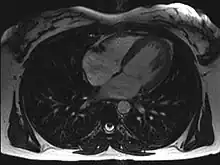

Magnetic resonance imaging (MRI)

Axial MRI image at the level of the heart

Magnetic resonance imaging visualizes the heart by detecting hydrogen atoms using superconducting magnets, particularly those attached to water and fat molecules.[9] These hydrogen atoms possess a property known as nuclear spin. Although the direction of this spin is usually random, the spin can be aligned using a powerful magnetic field.[9] Faint electromagnetic signals are emitted by these hydrogen atoms when their alignment is temporarily disturbed which can be detected and used to create an image of the heart.[10]

Cardiovascular magnetic resonance (MR) technology is able to measure the size, shape, function, and tissue characteristics of the heart in a single session.[11] It is also commonly used to determine ventricular function and for the evaluation of structural heart disease.[12] It is more reproducible than echocardiography with less inter-observer variability, allowing for more precise reference ranges to better distinguish health from disease.[11] Additionally, MR lacks ionizing radiation and does not have any known long-term effects, making it safe for repeated imaging.[13]

Additional benefits from cardiac MRI include the ability to detect scar within the heart using late gadolinium enhancement, and identify other abnormalities of the heart muscle itself such as infiltration with iron or amyloid protein.[11] Disadvantages of MRI include lengthy protocols and the potential for claustrophobia. Furthermore, an MRI scan cannot be performed in some people who have metallic implants such as some types of pacemakers, defibrillators, although many modern pacemakers are safe for use within an MRI scanner.[14] Other metal structures such as artificial valves and coronary stents are generally not problematic. However, MR is less widely available and may be more difficult for patients to tolerate than other noninvasive modalities, requiring physician monitoring for complex cases.[13]